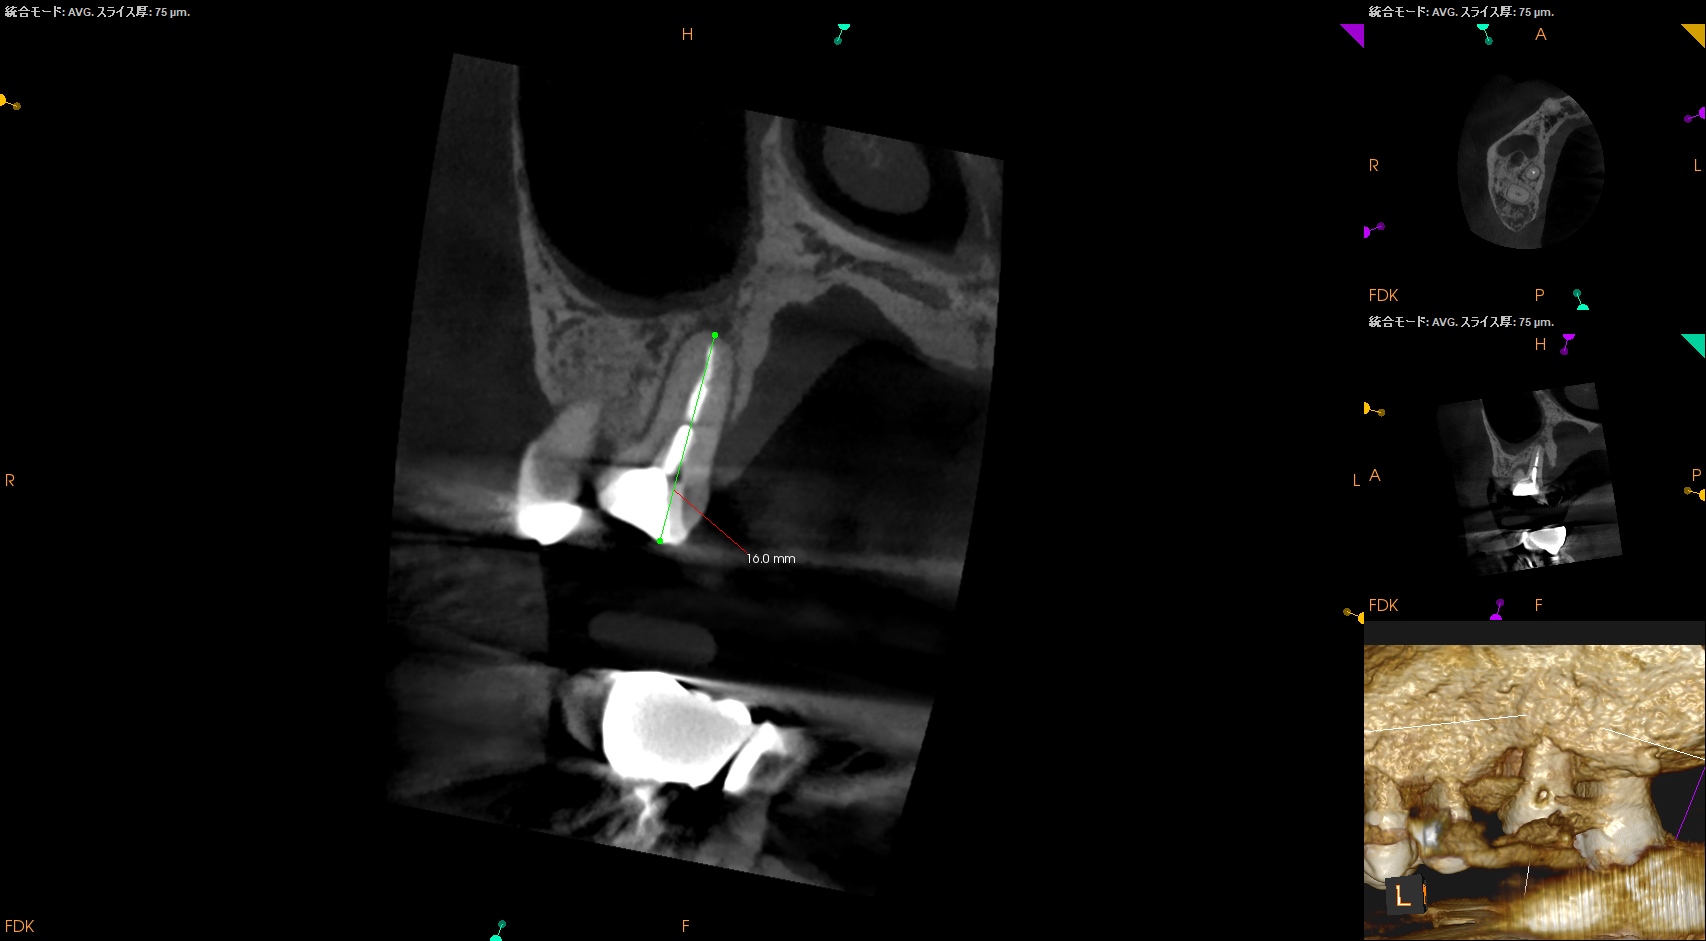

ちなみにPの再根管治療は、

作業長は16.0mm前後が予想される。

その際の作業長はCBCTから16.0mmである。